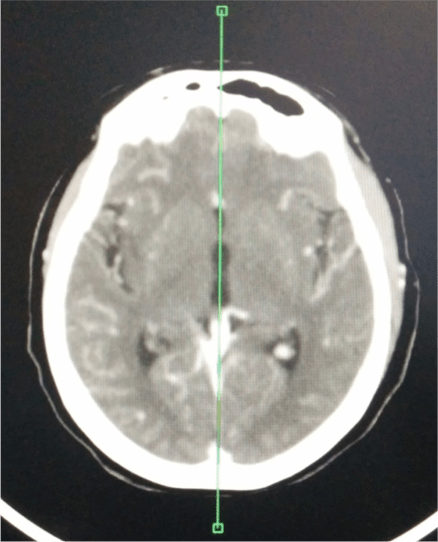

TC DE PERFUSIÓN.

Realizaremos un TC de perfusión fundamentalmente en estos dos supuestos:

- Cronología incierta.

- Ictus del despertar.

- Dudas diagnósticas.

El fundamento de la prueba consiste en administrar constraste iv y estudiar el primer paso de éste a través de la circulación cerebral (50 mL de cc; 4 mL/seg) a baja radiación (80 kVp; 150 mA). Se realiza un bloque de estudio de 4 cm a nivel de los ganglios basales (ya que a ese nivel encontramos los territorios de las ACA, ACM y ACP) y se aprovecha que el contraste pasa a través de la circulación cerebral produciendo hiperatenuación de los vasos, lo cual vamos a aprovechar para colocar un ROI arterial y otro ROI venoso que nos darán dos curvas de tiempo-atenuación de contraste

PASO 1º: COLOCAR LA LINEA MEDIA.

PASO 2º: DEFINIR VASOS. Colocación de los ROI.

- El ROI arterial debe seleccionarse en un arteria sana, preferiblemente en las ACA o en la ACM contralateral al lado infartado.

- El ROI venoso puede aplicarse por ejemplo en el seno venoso sagital superior o en la prensa de Herófilo.

PASO 3: MAPAS DE PERFUSIÓN

Tras la colocación de los ROI, se generan unos gráficos que deben estudiarse y verificar que:

- Las curvas deben tener un aplanamiento inical, luego un pico y finalmente un descenso = Indica que el contrasta ha pasado durante un tiempo adecuado.

- La curva venosa (azul) debe situarse más alto y con 1-2 segundos de retraso con respecto a la curva arterial (rojo). Este hecho indica una correcta entrada y salida del contraste.

Tras aplicar los ROI, el software de la estación de trabajo nos va a dar un mapa de la perfusión en forma de colorines codificados que nos van a aportar tres parámetros fundamentales (sacados de ecuaciones matemáticas,se denomina Deconvolución).

- Tiempo de tránsito medio (TTM): indica áreas isquémicas (puede sobreestimar un poco el tejido de verdad en peligro).

- Flujo sanguíneo cerebral (CBF): indica el área de isquemia crítica (es más específica que el TTM).

- Volumen sanguíneo cerebral (CBV): indica el área de necrosis ya instaurada.

El mapa del TTM debería ser el primero en analizarse ya que muestra las anomalías más groseras. Lo comparamos con un ROI con el parénquima contraleral normal y si está aumentado en la zona de sospecha diagnóstica, indica isquemia.

A continuación se estudian los mapas de CBF y CBV, los cuales son más específicos para distinguir la isquemia del infarto. La disminución del CBF indica zona de isquemia crítica, mientras que la disminución del CBV indica zona de necrosis ya instaurada. Esta es la diferencia.

Conceptos a tener claro:

- Hay un concepto llamado Mismatch que significa discordancia y que refleja precisamente esta diferencia anteriormente explicada. No concuerdan las áreas afectadas de isquemia y con las áreas ya necrosadas. Es equivalente a decir que de todo el territorio afectado por la isquemia (indicada por el TTM y CBF) hay una zona que ya se ha muerto del todo y no se va a recuperar (inidicada por el CBV). Cuando el mismatch es mayor del 20% hay que tratar al paciente.

- Penumbra = Tejido afectado/aturdido = Aumento de TTM ; Diminución del CBF ; Normal el CBV

- Core = Tejido necrótico = área afectada en el volumen = Aumento del TTM; Disminución del CBF; Disminución del CBV.

- Tejido salvable = TTM – CBV.

Lo que hemos visto antes es un análisis cuantitativo. A pesar de todo, en la urgencia puede ser incluso más util el análisis visual o cualitativo. Las casas comerciales han desarrollado incluso mapas resumen que muestren ese «mismatch» o discordancia de forma gráfica.

Se pintan unos mapas que muestran:

- Rojo = zona infartada. El volumen es menor de 2 litros.

- Verde = zona isquémica salvable (TTM – CBV). TTM mayor del 145% y volumen mayor de 2 litros.